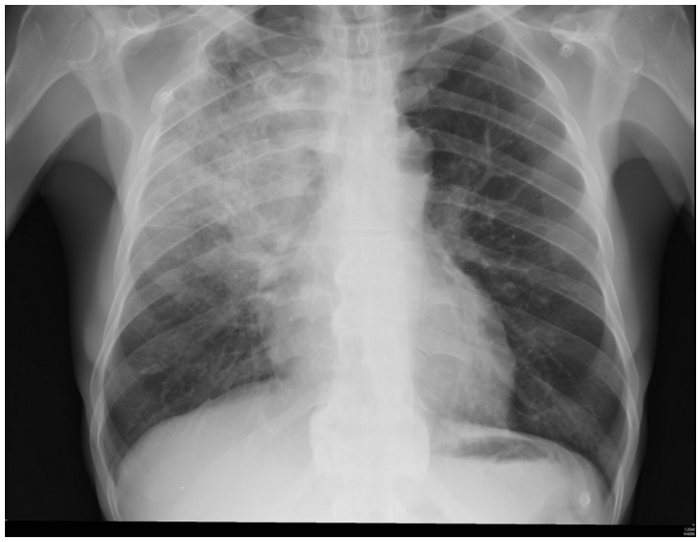

.......Um paciente de setenta anos de idade, com queda do estado geral e inapetência há cerca de três dias, previamente hipertenso e diabético, apresenta-se sonolento e pouco responsivo, com PA de 100 x 60 mmHg, TEC de 4 segundos e FC de 126 bpm. Seus familiares contam que ele tem quadro de tosse produtiva há cerca de uma semana. Exames disponíveis: Hb 14; leucócitos 10.000; plaquetas 200.000; Ur 40; e Cr 1,2. O RX do paciente é mostrado abaixo.

Internet: <https://www.todoestudo.com.br/wp-content/uploads/2018/02/pneumonia.jpg>.